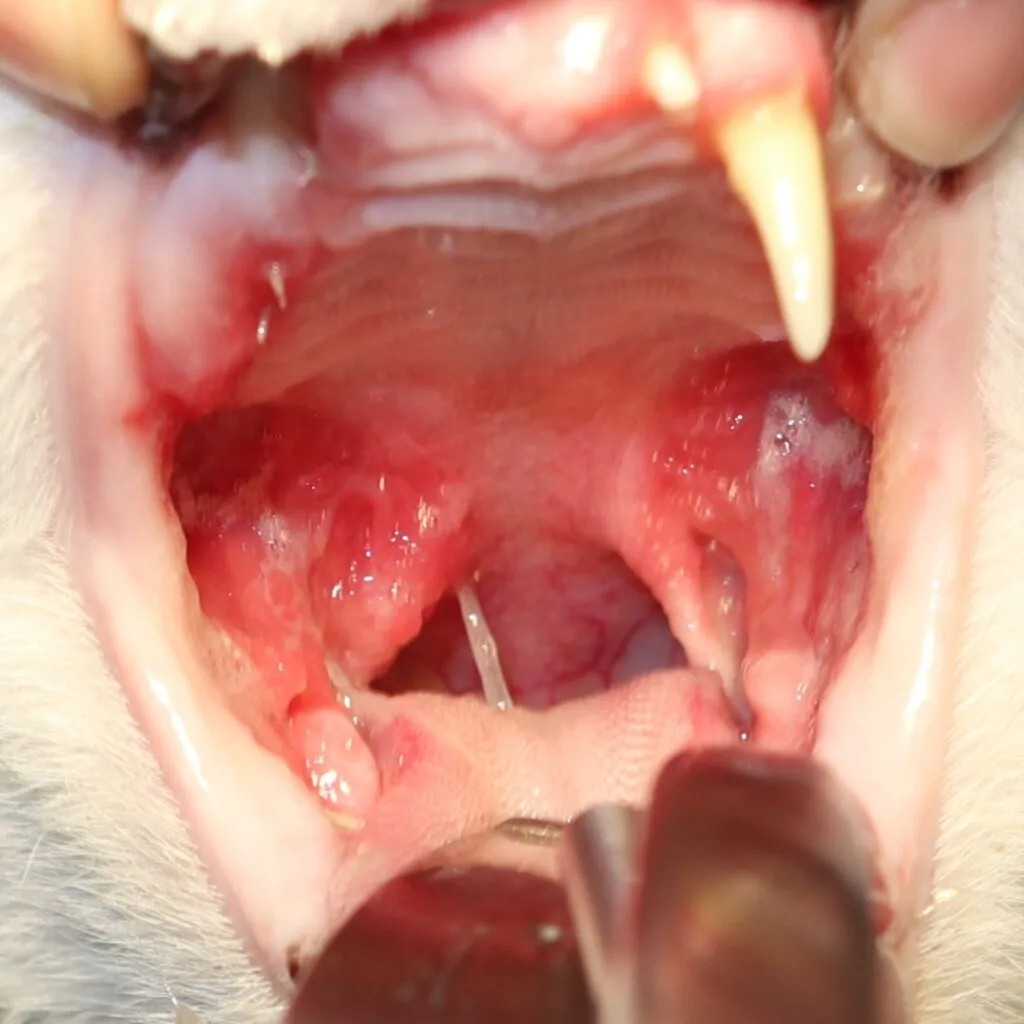

9 歳の猫ちゃん(約5 kg)の口内炎治療🦷

Before

処置中

この子は、重度の口内炎で食事がとれず、よだれが多い状態でした。

口内炎の治療は大きく分けて内科療法と外科療法があります。

内科療法では改善が乏しかったため、麻酔をかけ全ての歯の抜歯をおこないました。

小さくて見えにくかった小さな歯もマイクロスコープにより認識しやすくなりました。

処置後は内科療法を継続し、1年後には炎症もだいぶ引いたのが分かります。

現在は、痛みやよだれもなくご飯を食べられるようになりました🐱